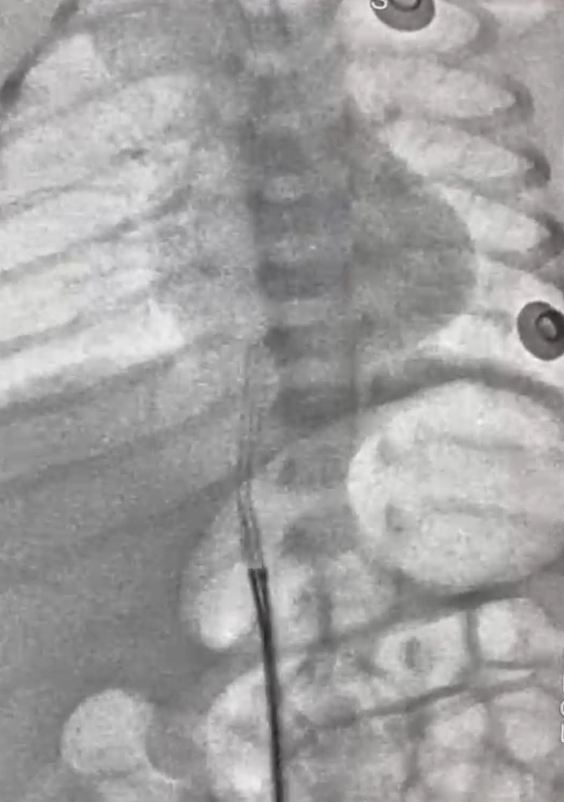

وأفاد أ. د. محمد عبد الهادى.. عميد معهد القلب القومى بأن طفل حديث الولادة، يبلغ من العمر ٥ أيام فقط، قد وصل إلى المعهد في حالة حرجة، بعد أن تحرك جزء من قسطرة السرة من مكانه واستقر في قلب الطفل، وهذه القسطرة تستخدم أحياناً لإدخال السوائل والأدوية، وقد استدعت هذه الحالة تدخلاً سريعًا ودقيقًا، وعلى الفور قام فريق عمل الحضانة، وعلى رأسهم الدكتور/ محمد سعد سلطان.. زميل الأطفال، فى التنسيق لدخول الحالة أول أيام العيد وتجهيزها للتدخل الجراحى، وقام فريق طبي متميز بإجراء القسطرة العاجلة للرضيع. وبفضل الله ومهارة الفريق الطبي، تم استخراج قسطرة السرة بنجاح ودون مضاعفات، والرضيع الآن في حالة مستقرة، وقد غادر الحضانة إلى منزله في حالة جيدة وبدون أي مضاعفات.

وأضاف عميد المعهد أنه ساهم في هذا الإنجاز الطبي فريق متكامل من الأطباء والتمريض والفنيين من أبناء المعهد تحت قيادة أ. د. أحمد معوض الإمام إستشارى القلب وقسطرة العيوب الخلقية بالمعهد، وأ. د. رشا حسني.. رئيس قسم التخدير، وأ. د. أحمد جمال ندا.. زميل التخدير، د. هبة وشاحى .. استشارى الحضانات والرعاية، ود. أحمد أبو هاشم ود. محمود صديق، ود. نعمة إبراهيم، ود. جهاد محمود.